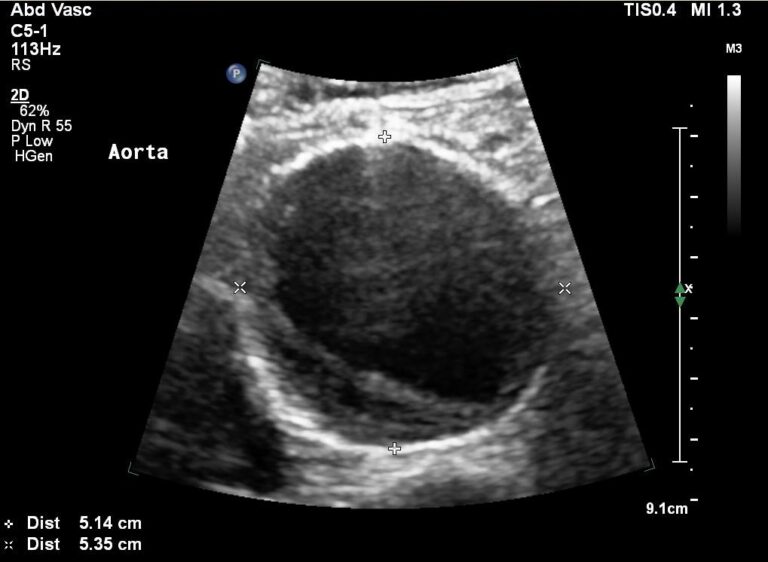

ΥΠΕΡΗΧΟΙ ΑΝΩ-ΚΑΤΩ ΚΟΙΛΙΑΣ

ABDOMINAL ULTRASOUNDS